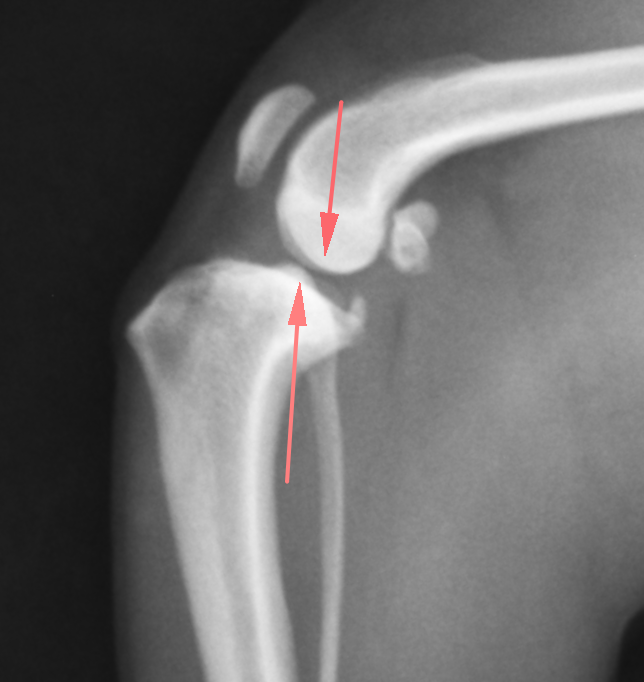

正常な膝関節のレントゲン画像です。大腿骨と脛骨のライン(矢印)がほぼ一致しているのがわかります。

前十字靭帯断裂の膝関節です。ずれているのがおわかりでしょうか?

矢印を入れたものです。正常なものと比較すると一目瞭然でずれているのがわかるかと思います。